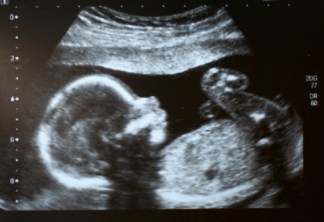

>> Animation échographie (Vidéo, animation)